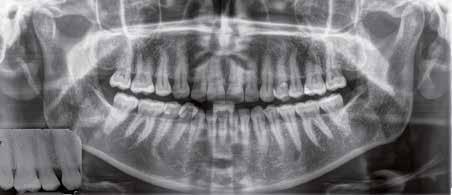

Hölgy páciensem az első konzultáció során tipikus kórtörténetet vázolt fel: Gyermekkora óta szeretett volna fogszabályozó készüléket, hiszen mindig is zavarta a class 2-es eltérésnél tipikusan jellemző nagy overjet (1-3. képek), és természetesen az ezáltal kifelé álló felső metszőfogai, részben a felső metszők protrúziója, részben pedig a disztálisan elhelyezkedő mandibula miatt. Annak ellenére, hogy több fogszabályozó szakorvosnál is járt az évek során, de mivel saggitális eltérése és az alsó metszőfogak torlódása miatt négy kisőrlőfog extrakcióját, illetve emellett sokszor állcsont műtétet is javasoltak neki, nem vágott bele a kezelésbe (4-5. képek).

A fogorvosa – nagyon helyesen – felhívta a figyelmét, hogy parodontális státusza is valószínűsíthetően romlani fog az eltérése miatt, újabb kört futott, immár 39 évesen, de még mindig premoláris fogak húzása és állcsontműtét nélkül szerette volna a fogszabályozást.